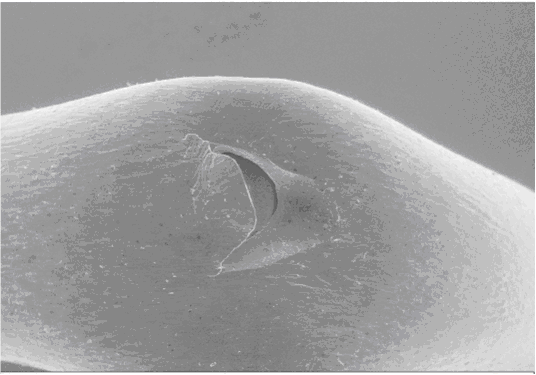

Bild 1

Auf Bild 1 ist der Riss in seiner Gesamtheit zu sehen, der Katheter ist, um den Riss aufklaffen zu lassen, für das Bild gebogen worden.